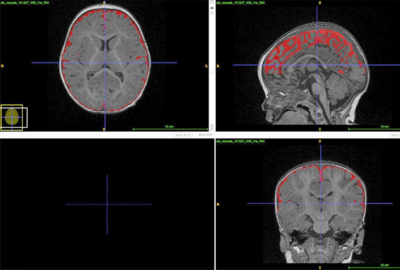

Ashura Buckley surveillait l'activité cérébrale nocturne d'enfants autistes ou présentant un retard de développement à l'aide de l'électroencéphalogramme (EEG) et a remarqué que leurs schémas d'ondes cérébrales étaient étonnamment différents de ceux de leurs pairs neurotypiques.